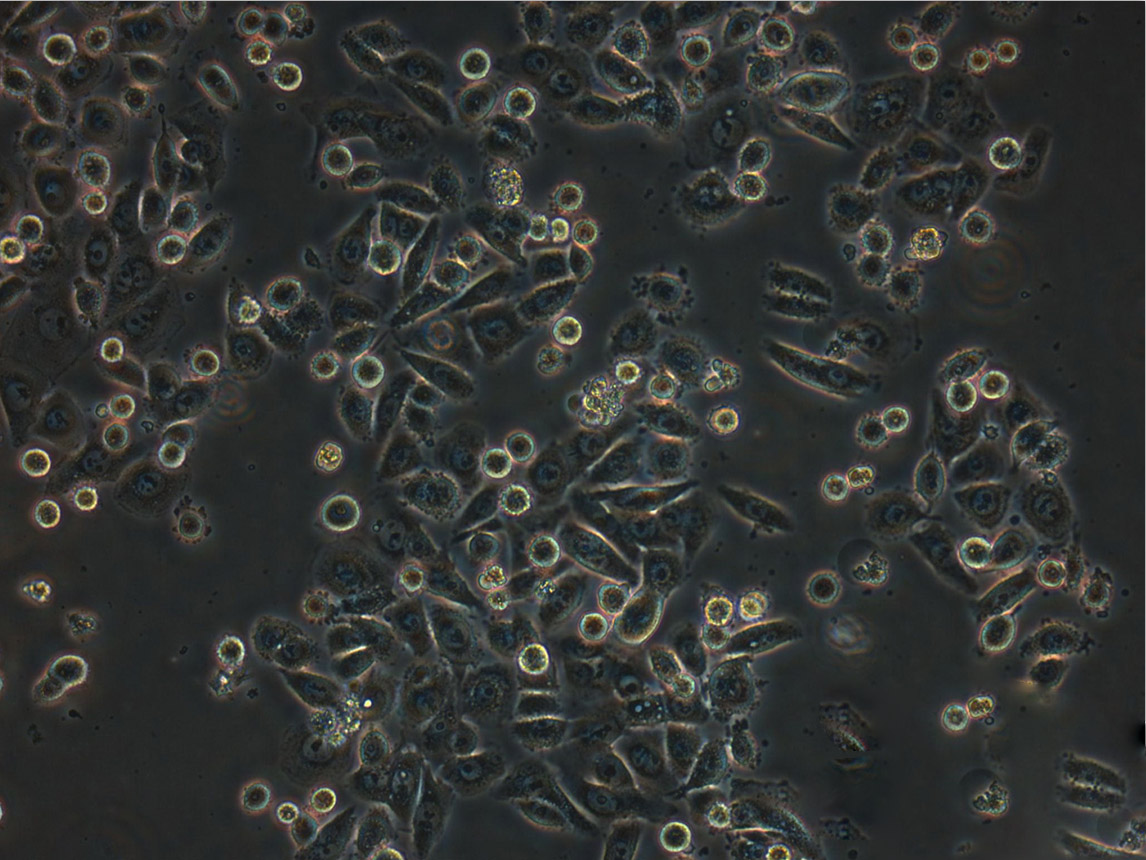

细胞生长:贴壁

细胞背景资料:乳腺癌;胸腔积液转移;女性

细胞形态:上皮细胞样

细胞生长特性:贴壁